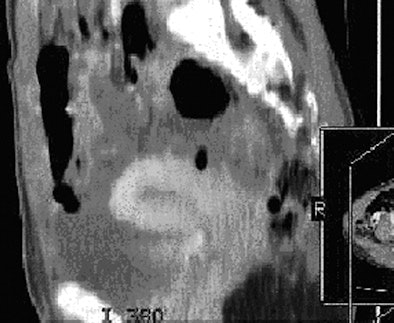

![]() |

| Thirty-four-year-old woman with normal endometrium. Axial contrast-enhanced CT image (above) shows prominent triangular-shaped endometrium. Number 1 and circle indicate incidental measure of ovarian cyst not relevant to endometrium or this article. Sagittal reconstruction image (below) of same patient shows normal thin endometrium on this magnified image. Images courtesy of the American Roentgen Ray Society; from Grossman J, Ricci Z, Rozenblit A, et al. Efficacy of contrast-enhanced CT in assessing the endometrium. AJR. 2008;191:664-669. |